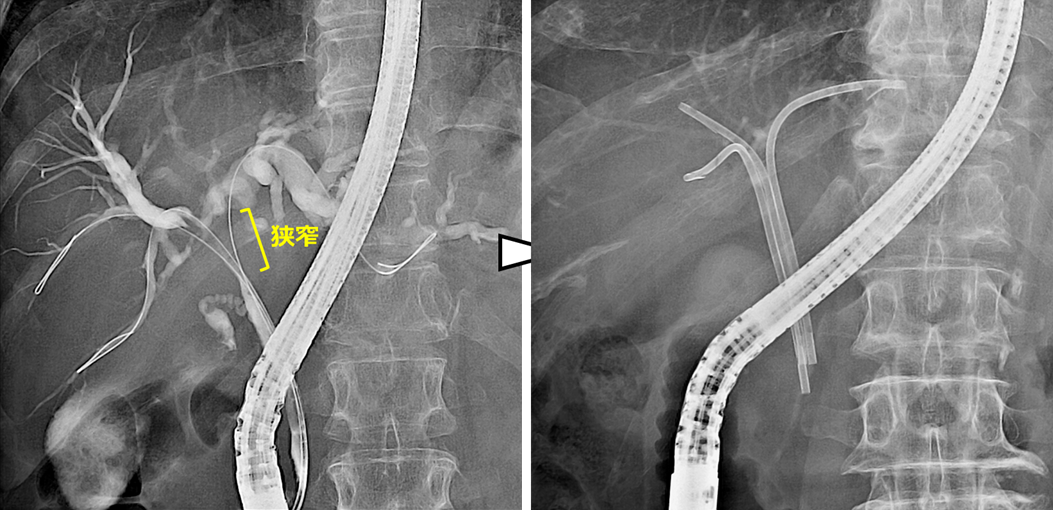

術後の良性胆管空腸吻合部狭窄に対する胆道ドレナージと拡張術

(十二指腸癌で膵頭十二指腸切除術、Child再建後)

膵頭十二指腸切除後に胆管空腸吻合部の狭窄を認めた症例です。

手術後1年が経過した頃に肝胆道系酵素の上昇を指摘され、内視鏡治療を行いました。胆管空腸吻合部に良性の狭窄を認めたため、狭窄部に対して金属ステントを交差するように留置しました。ステントは2~3か月程度留置した後に抜去することで、吻合部の狭窄は改善しました。

内視鏡治療後は肝胆道系酵素も改善し、その後は吻合部狭窄の再発も認めていません。